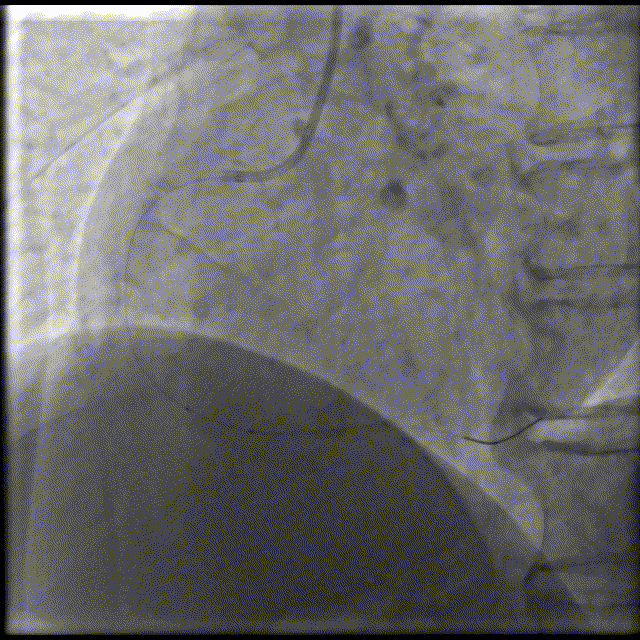

Telescope™导引延长导管辅助下,BAT技术,导引延长导管深达第二转折处,2.75x28mm支架顺利到位,12atm释放。

• 即刻结果:支架成功植入

• 远期结果:随访,强化抗血小板

• 后期的处理?可能存在的风险?:支架血栓风险,近中段内膜有否损伤